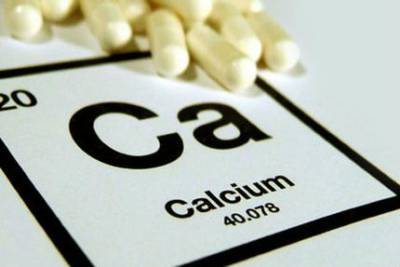

- hiányosság az étrend gazdag élelmiszerek kalcium-;

- D-vitamin hiánya a szervezetben;

- 2-es típusú, vagy szenilis. Ez akkor fordul elő, azonos gyakorisággal nők és férfiak egyaránt. Főként embert érint után 70-80 év, lassan alakul ki, társul a korral járó változásokat a szervezetben, a kalcium hiánya az étrendben, a D-vitamin a szervezetben.

A kalcium hiánya az étrendben lehet az oka a csontritkulás

A fő cél az étrend - teljes kalcium biztosítása és javítása az asszimiláció a csont- és termékek kivételével, amelyek megsértik a mikrotápanyag felszívódása a gyomor-bél traktusban.

Emellett a kalcium és D-vitamin, a diéta csontritkulásban szenvedő tartalmaznia kell egy sor egyéb anyagok, amelyek segítenek helyreállítani csontszerkezet (vitaminok, ásványi anyagok).

Az első csoportba a kalcium-és D-vitamin, amelyeket mind a kezelésére és megelőzésére. Ez magában foglalja a flavonoidok, amelyek gátolják a csontreszorpciót és serkentik az oktatás és csontenyvet-hidroxi-komplexum, amely lehet használni, még a terhes nők és szoptató anyák.

- Monitor a kalcium mennyisége jut a szervezetbe, hogy az ásványi kiegészítők és gyógyszerek orvos által felírt, ha szükséges.